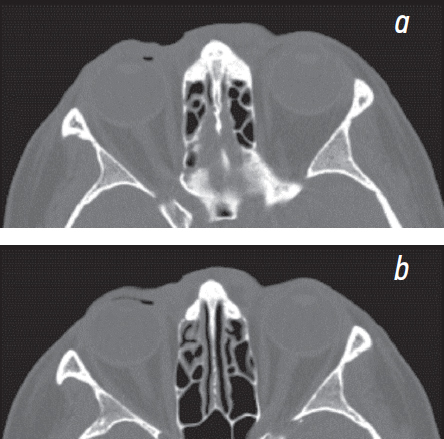

Despite clear signs of non-suicidal self-inflicted injuries in the patient, surgical treatment was required for cicatricial lagophthalmos. Surgical treatment was preceded by spiral computed tomography of the orbits to assess the state of tissues in the proposed surgical site and exclude the presence of silicone. Data on the presence of silicone in both the orbit and surrounding tissues have not been received. In the upper eyelid, an air bubble was detected in the skin pocket at the edge of the wound (Fig. 3, a, b). Compared with air, silicone has a much higher, close to bone, density.

Fig. 3. Spiral computed tomogram of orbits. a, b – air bubble at the right of the upper eyelid area / Рис. 3. Спиральная компьютерная томограмма орбит: a, b — пузырёк воздуха в области верхнего века справа